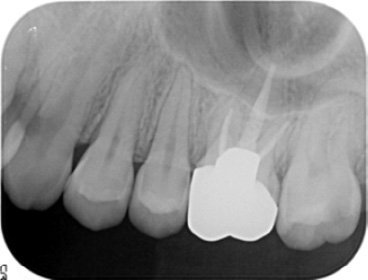

右上のレントゲン写真では、真っ白く映っている部分が金属の被せ物です。